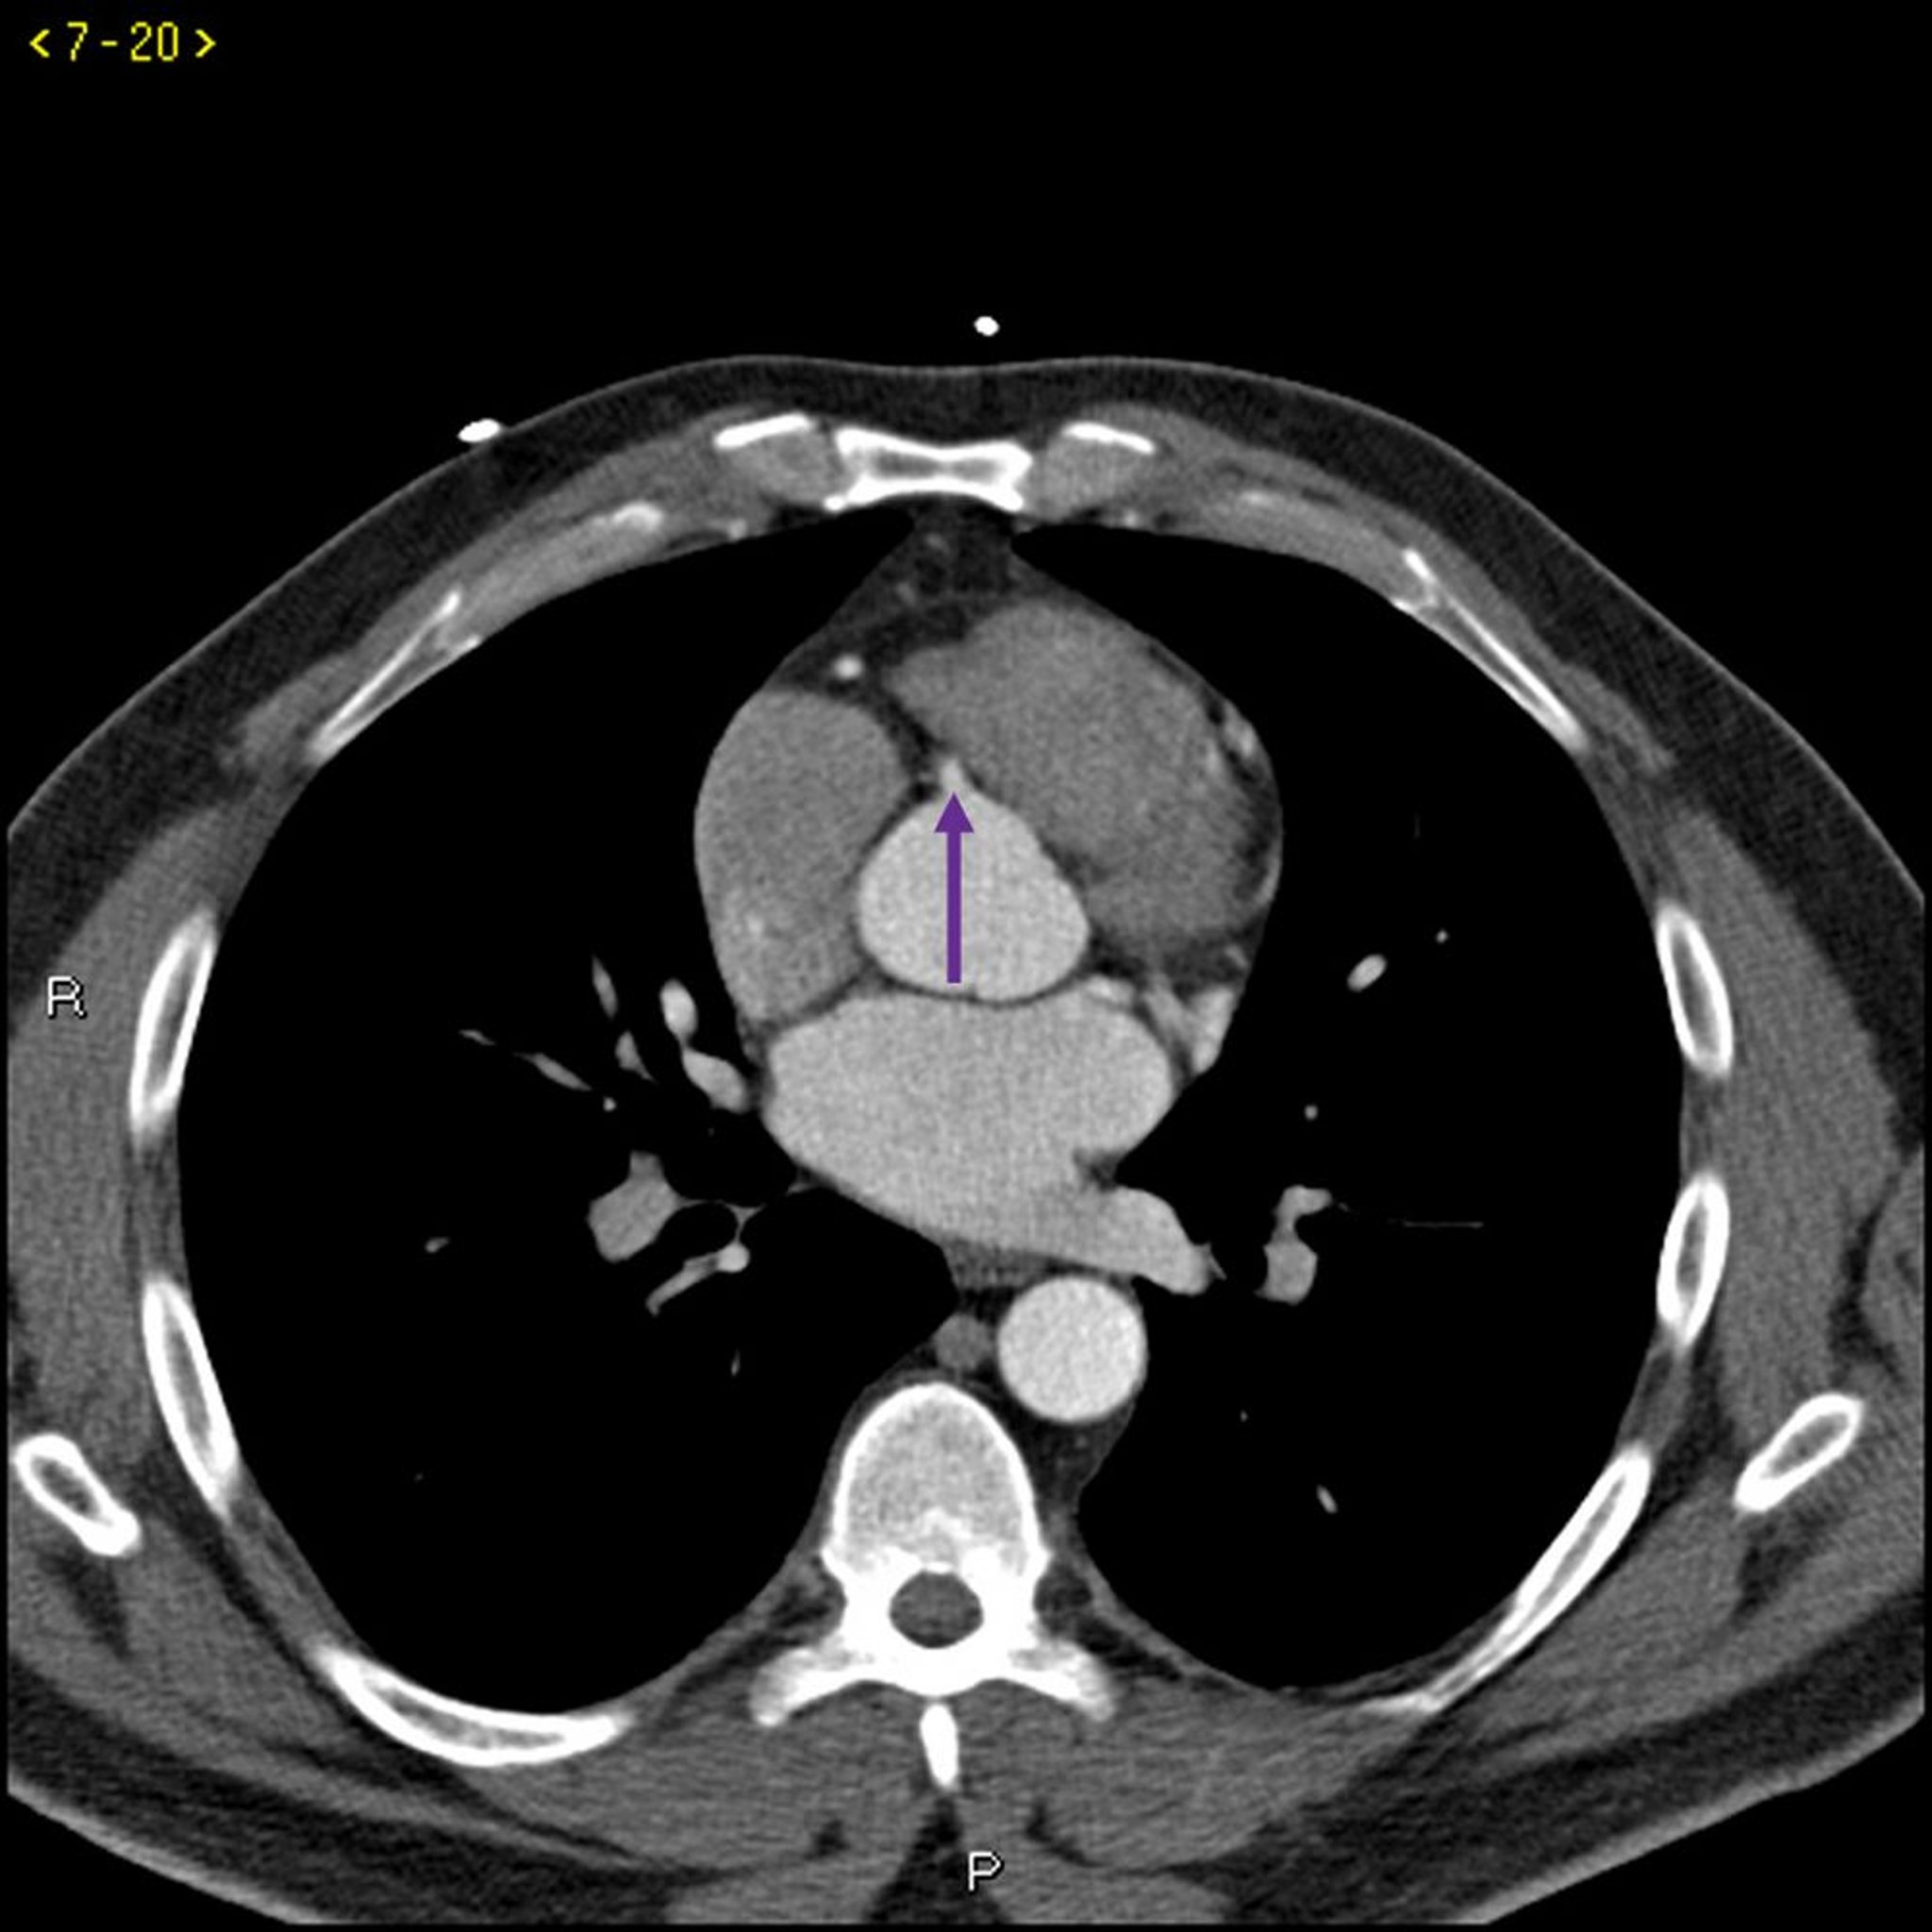

Phim chụp CT có thuốc cản quang cho thấy các động mạch vành bình thường – Lát cắt 5

Phim chụp CT có thuốc cản quang này cho thấy các động mạch vành bình thường. Động mạch chính bên trái được biểu thị bằng mũi tên màu đỏ. Động mạch vành xuống trước trái và động mạch mũ trái lần lượt được biểu thị bằng mũi tên xanh lá cây và xanh lam và động mạch vành phải được biểu thị bằng mũi tên màu tím.